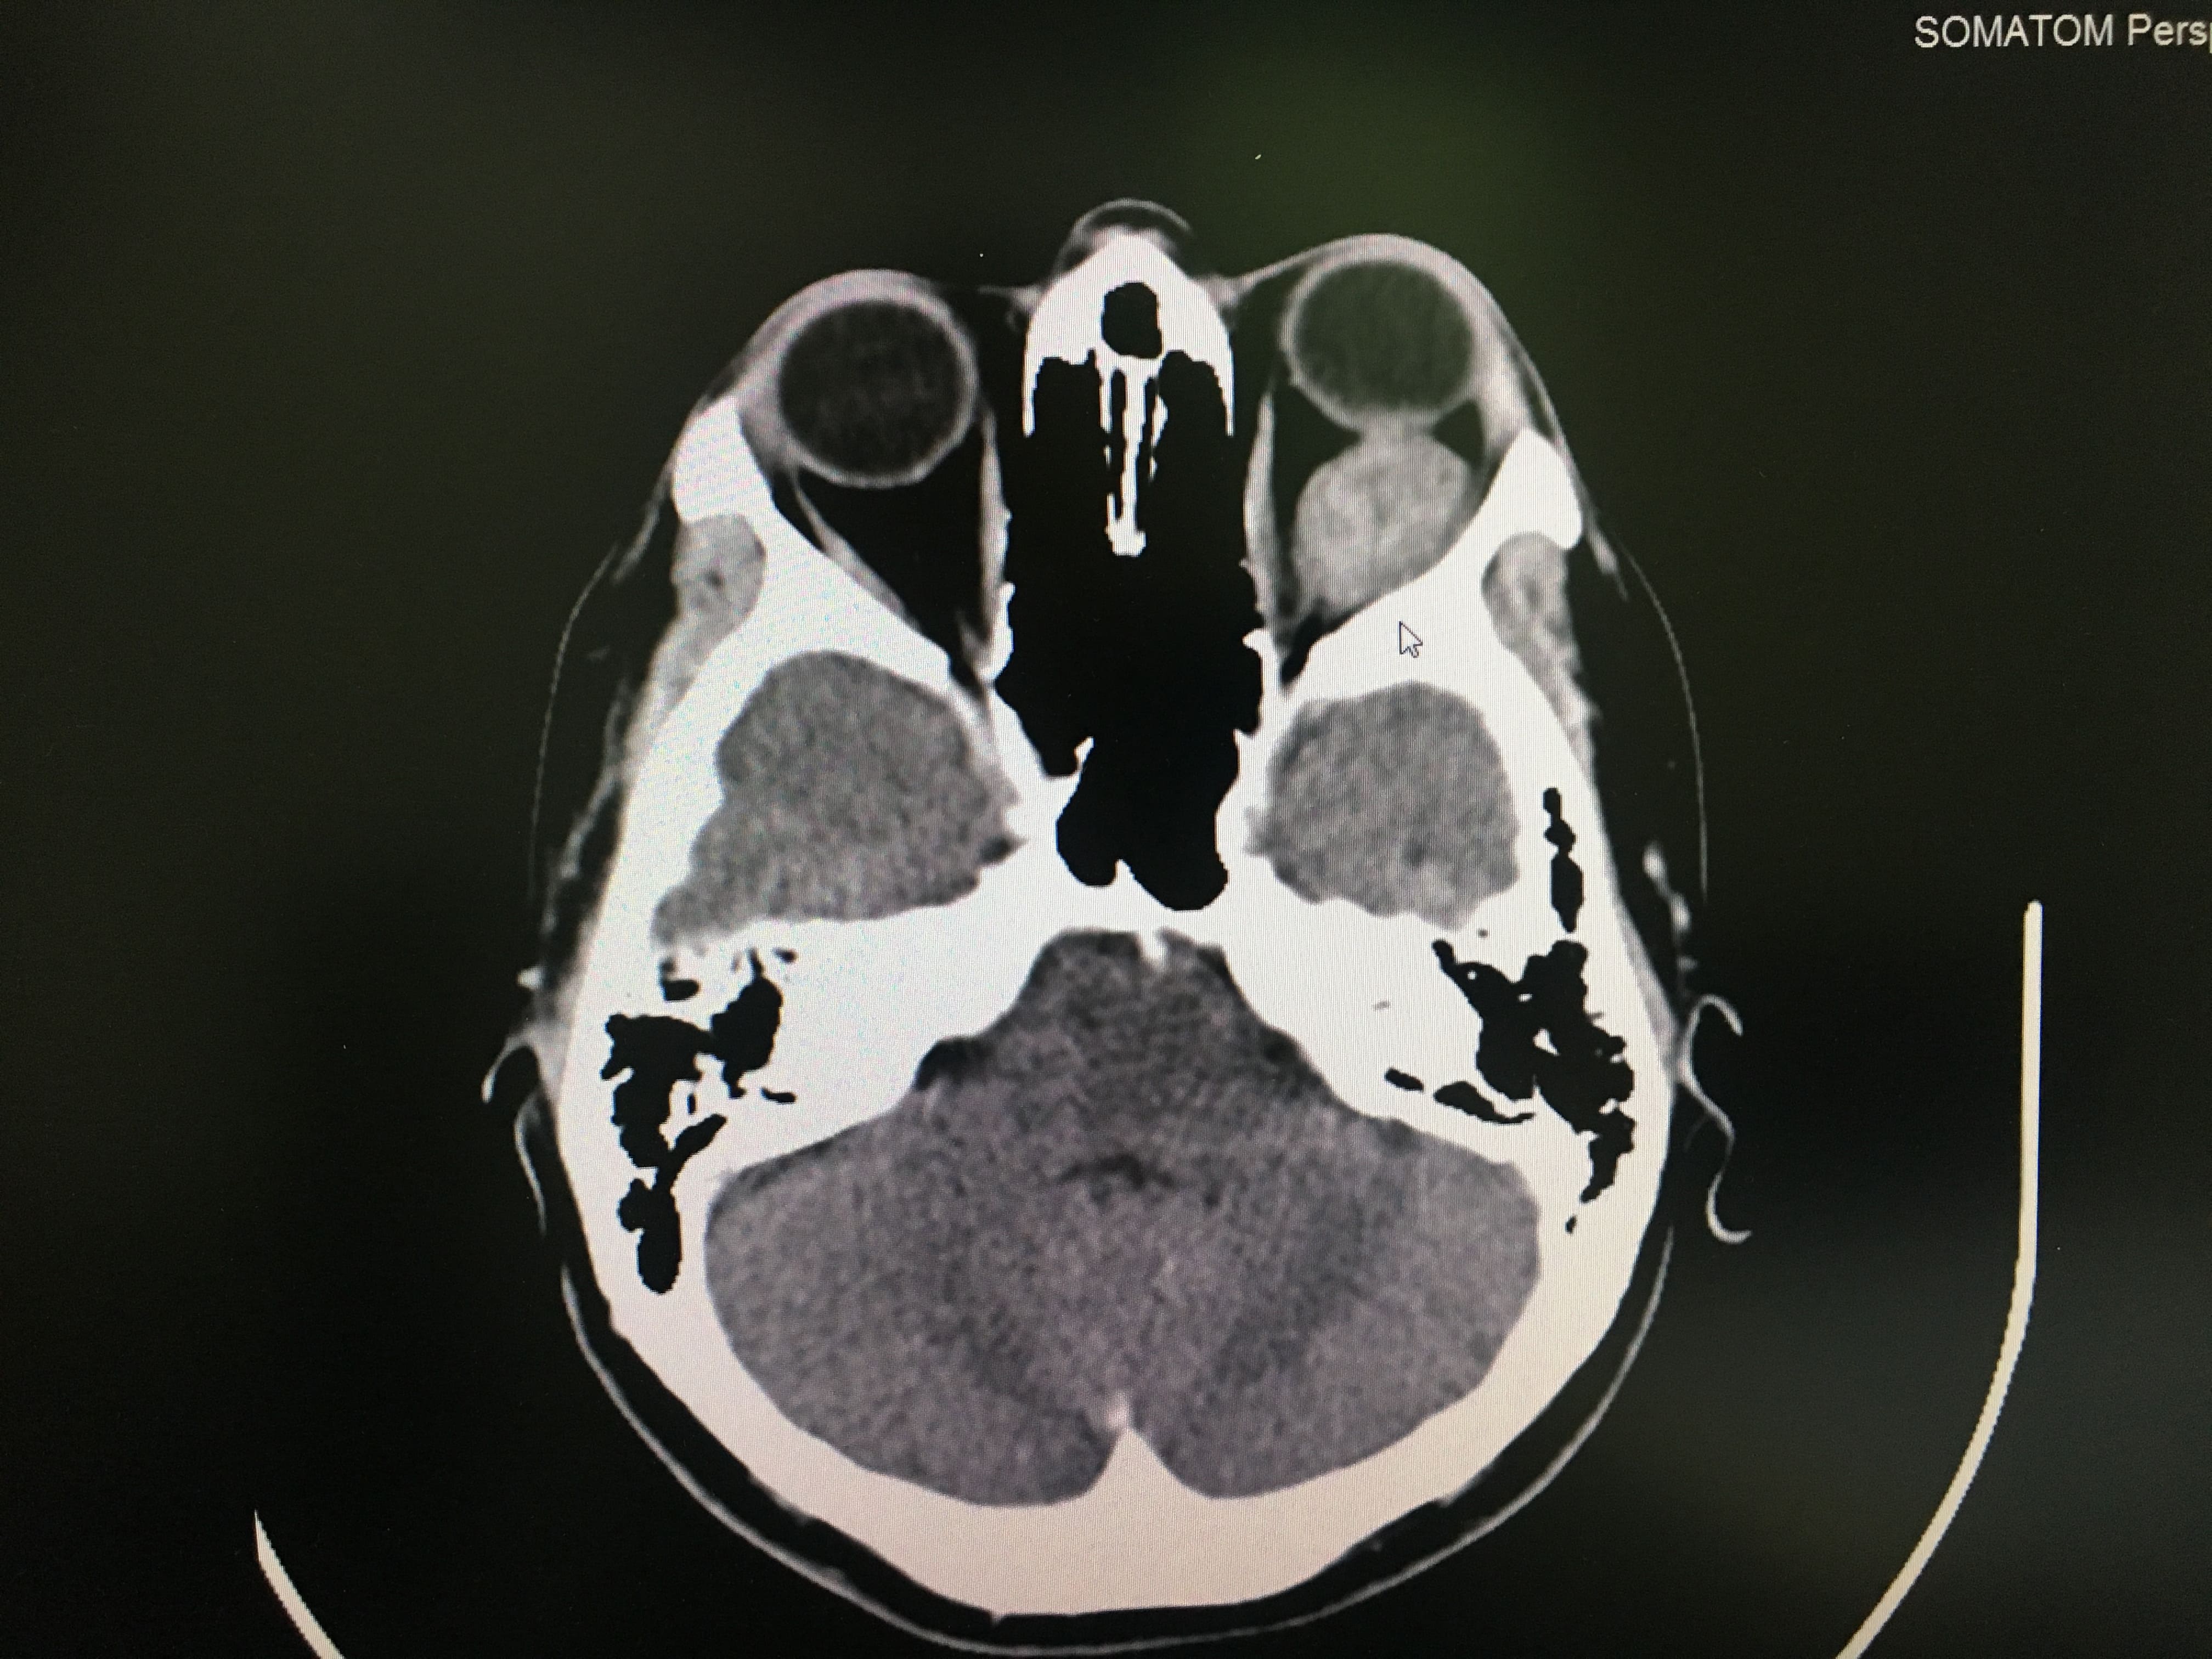

- Patología de orbita